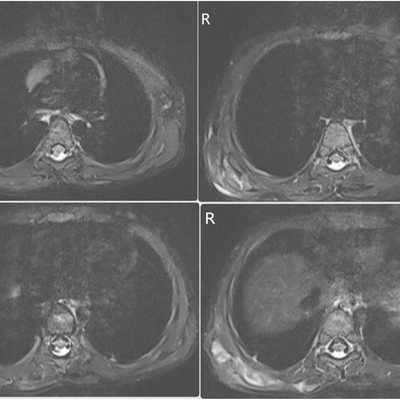

Click on an image below to view more info.